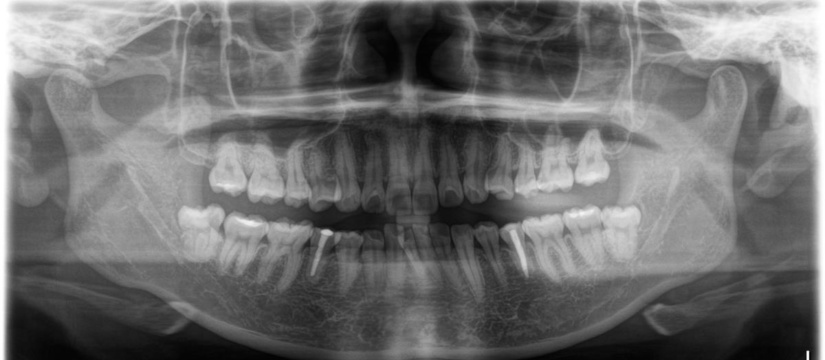

歯科治療にはレントゲン画像が欠かせません。レントゲンは放射線被曝をいたしますが、このレントゲンは被曝量が極めて少ないのが特徴です。国民感情として被曝線量に強い関心があるドイツで製作されたものですので、他社のレントゲンと比較しても低被曝です。被ばく線量が低いとレントゲンが綺麗に写らないというジレンマがあるのですが、それをクリアーにしたのがこのレントゲン装置で、低被曝量にもかかわらず、他社を圧倒する高画質のレントゲンが撮影できます。

飛行機は高いところを飛ぶために宇宙線というものに被曝いたします。歯科で一般的に撮影するパノラマレントゲン写真を当機で12回撮影すると、だいたい飛行機で東京とニューヨークを往復した被曝量に相当します。